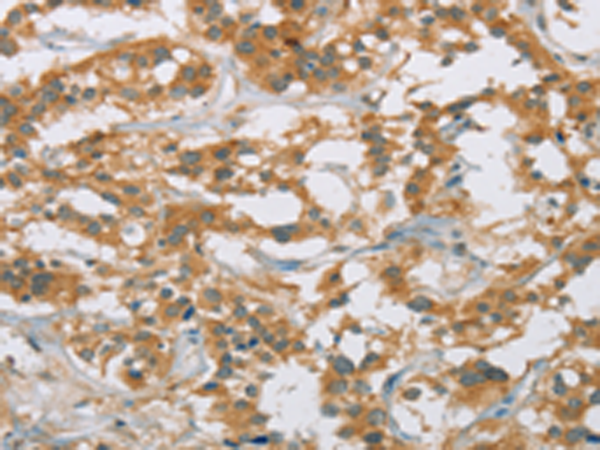

分类: 科研抗体货号: P08182别名: p38; CRKII应用: IHC反应种属: Human, Mouse, Rat